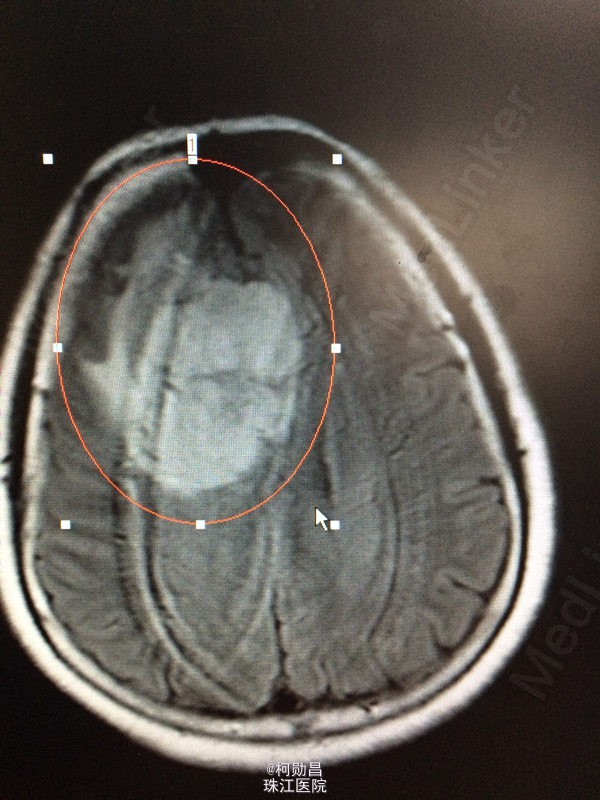

患者 62岁女性,因“发现右侧大脑镰旁肿物2天”入院,症状表现为:反应迟钝,懒言,无其他症状。MR提示“右侧大脑镰旁肿瘤,考虑脑膜瘤”